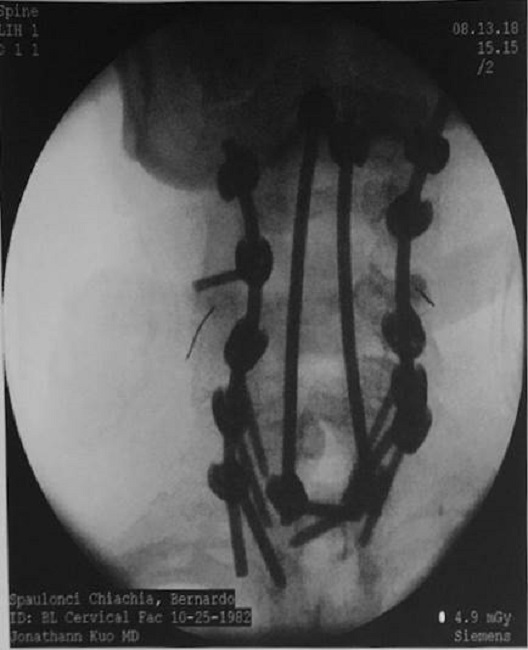

Senti o baque e, com tristeza, percebi que minha perna esquerda não estava se movendo, e isso me deixou perplexo. Frustrado e assustado, procurei socorro, e, após uma semana de ligações, encontrei o Dr. Q, e sua sugestão foi, antes do aperto de mão, que a única forma de sair dessa situação seria uma intervenção cirúrgica. De acordo com os prontuários emitidos em 14 de setembro de 2017, após a obtenção tanto de uma radiografia, de EOS, quanto de tomografia e ressonância magnética, eu apresentava espondiloloptose de C6 com uma quantidade significativa de displasia de ambos C6 com anterolistese até o toque Anterioridade de C7 e T1, com um C7 displásico e uma parte displásica de T1. Era a medula espinhal colidindo significativamente sobre a parte póstero-superior de C7, onde apresenta-se estenose medular significativa neste segmento, tornando-me mielopático.

Eu também tinha o bloco de fusão automática de C1, C2 a C3, conforme registros médicos a seguir:

O paciente tem história de síndrome de Larsen com várias cirurgias anteriores nos membros inferiores. A dor tem sido refratária ao manejo não operatório. Após uma discussão aprofundada dos riscos, benefícios e alternativas, o paciente decidiu prosseguir com a correção cirúrgica. Os riscos foram amplamente discutidos com o paciente, incluindo, mas não se limitando à persistência da dor, agravamento da dor, paresia, paralisia, morte, pseudoartrose, ruptura dural e a necessidade de cirurgia futura. O paciente entendeu os riscos e benefícios e decidiu prosseguir. (Registros médicos # 12274061, p.2).

Então, depois que o Dr Q discutiu meu caso com Dr. T,- o chefe do departamento de cirurgia ortopédica, bem como com vários outros cirurgiões de coluna, ele decidiu fazer o procedimento com uma laminectomia posterior em C5, C6 e C7, permitindo que o cordão fosse coberto posteriormente, possibilitando a descompressão desta área e, então, fundando-o com C2 possivelmente até T3. Como essa operação médica era perigosa e difícil, o diretor de Cirurgia de Deformidade Espinhal do Hospital NYU Langone também foi designado para acompanhar o meu caso. Em outras palavras, a coluna cervical foi unida e fusionada até os ossos do peito, e o procedimento foi feito após uma incisão na nuca. Eles me mantiveram sob sedação por 11 horas. Fiquei no Hospital Ortopédico Langone da NYU por seis dias. Em 10 de outubro, usando um colar cervical, tive alta hospitalar e, em casa, o meu caminho de cura estava prestes a começar.